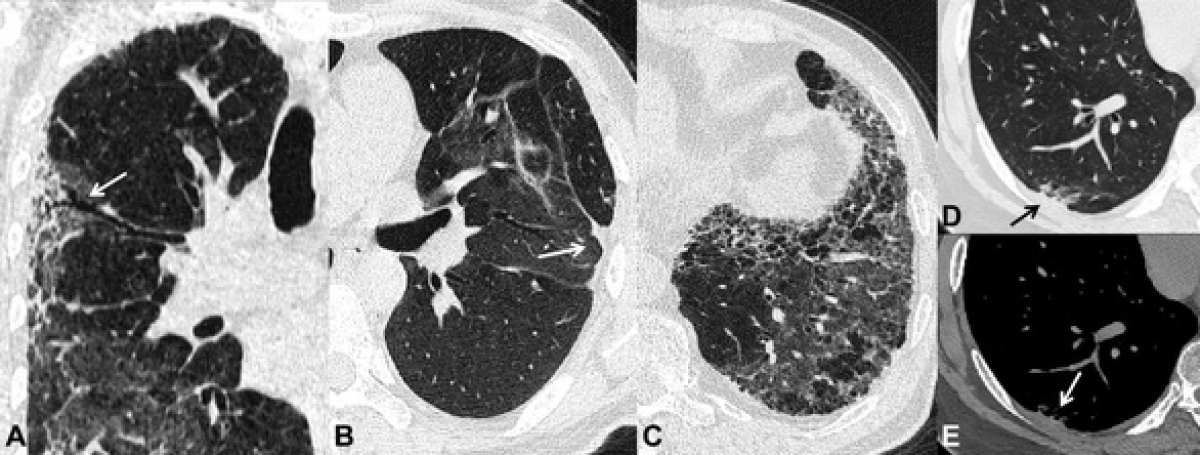

Tình trạng xơ hóa này có thể được nhìn thấy trên mô bệnh học qua sinh thiết phổi hoặc hình ảnh xơ trên phim CT scan. Đi kèm với nó là tình trạng giảm thể tích phổi và giảm độ khuếch tán của phổi qua các thăm dò chức năng hô hấp.

Trên phim chụp CT scan ngực, hình ảnh xơ hóa phổi biểu hiện dưới nhiều dạng và mức độ như: hình ảnh dải xơ, dày các vách liên tiểu thùy, hình ảnh lưới, dãn phế quản co kéo và điển hình nhất là hình ảnh tổ ong